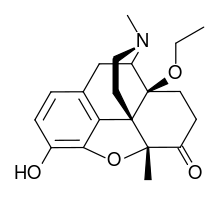

- 6-Keto Nalbuphine

6-Keto Nalbuphine 6-Keto Nalbuphine |